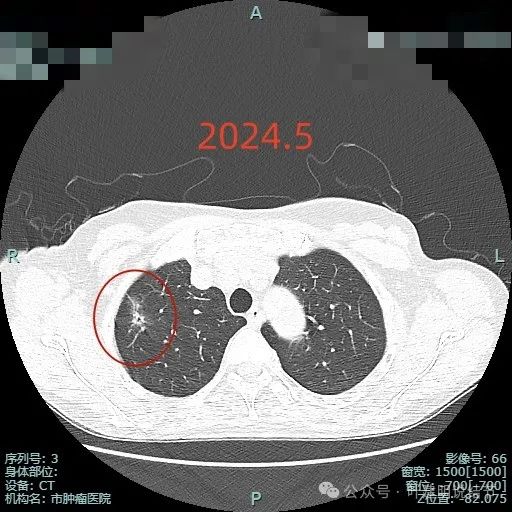

2024年5月时病灶范围较前扩大,灶内实性成分占比增多,毛刺明显,表面不平,分叶可见。

2024年12月显示出更大范围,以及更多占比的实性成分,边缘毛刺更多更典型,从影像上看已经很符合浸润性腺癌的表现了。